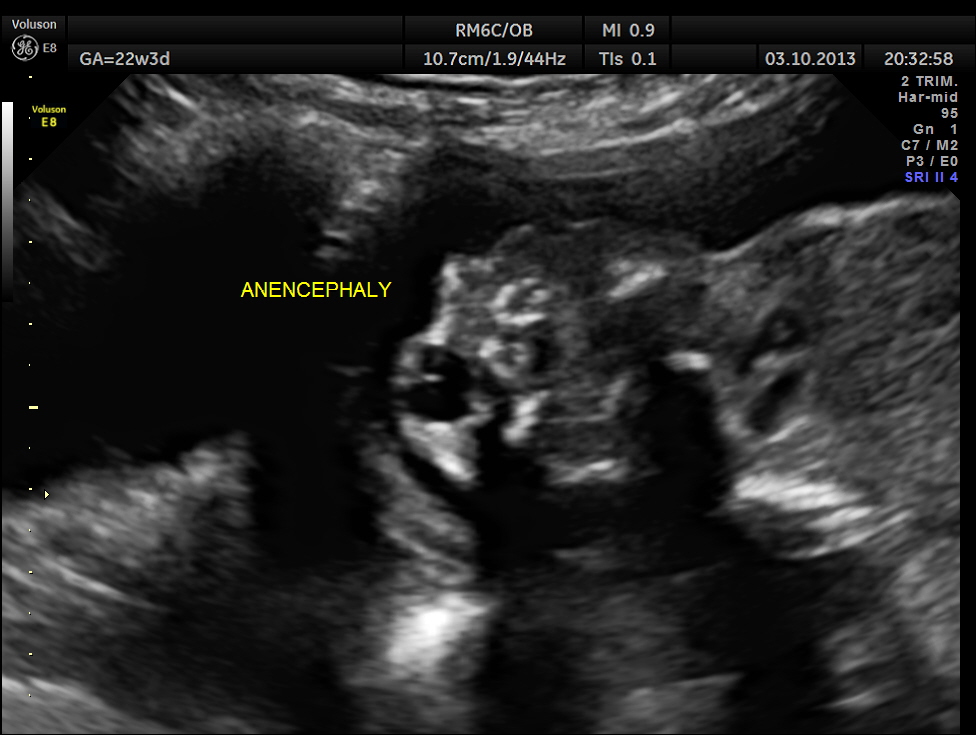

This was 20 year old primi , who was sent for routine anomaly scan around 22 weeks of gestation. There was no history of consanguinity. She had undergone 2 scans earlier , one at 7 weeks and another at 9 weeks. In between ,according to the patient she was not advised scan when she went for her ante natal clinical check ups.

The scan revealed anencephaly , which would have been picked up , if a scan had been done any time after 12 weeks of gestation. That was a depressing thought.

This fetus had anencephaly , horse shoe kidneys and abnormal appearance of spine .